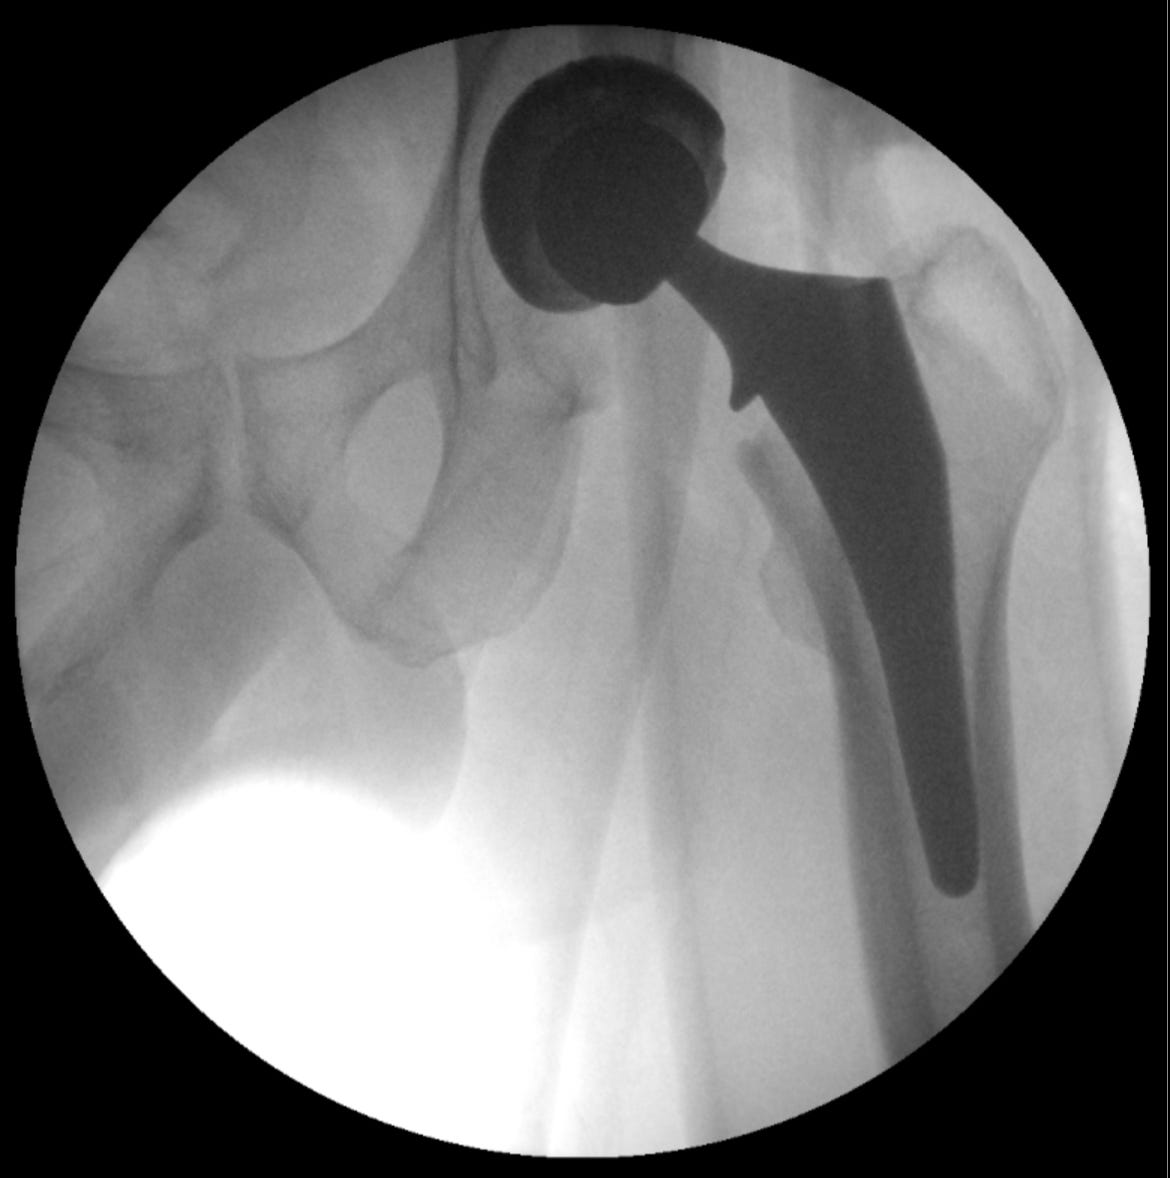

Lest you think I’m kidding about the new joints, consider the following. Now all I have to do is teach them to act like my old joints.